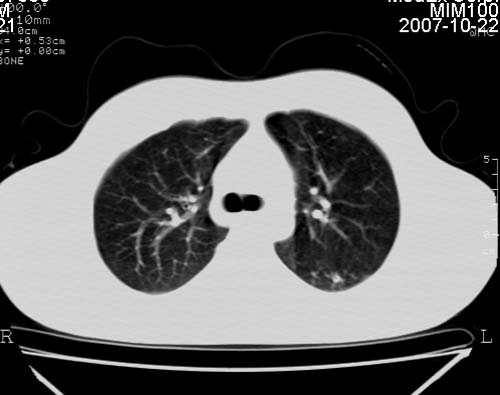

男,21岁,咳嗽、胸闷、乏力伴多汗二十余日、无明显发烧。患者一般情况好,为初三学生。

右肺上叶前段及左肺下叶多形性病变伴厚壁空洞,周边示树芽征.左肺下叶不张改变.

考虑;肺结核,不除外左肺下叶支气管内膜结核.